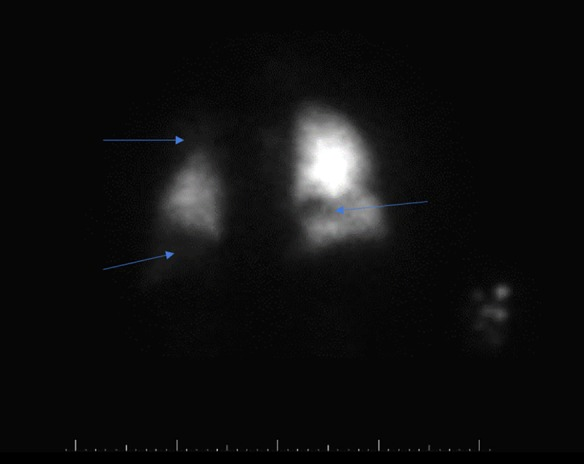

由于患者既往有深静脉血栓病史 , 并且出现急性右心负荷加重的表现 , 需要进一步检查评估是否存在肺栓塞 。 由于患者患有肾功能不全 , 不能接受CTA检查 , 于是进行了放射性核素肺通气/灌注扫描(V/Q) , 结果显示肺栓塞可能性很高(图2) 。

图2 放射性核素肺通气/灌注扫描(V/Q)图像